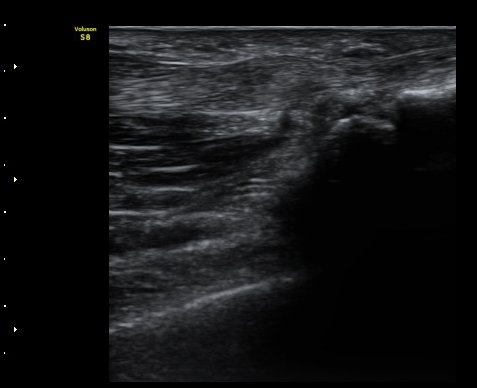

ÃÊÀ½ÆÄ °Ë»ç

ÈûÁÙÀÇ Á¾´Ü¸é°Ë»ç¿¡¼­ A1 ȰÂ÷(pulley)ÀÇ Àú¿¡ÄÚ ºÎÁ¾°ú ȰÀÚ ±ÙÀ§ºÎ¿¡¼­ ÈûÁÙÀÇ

ºÎÁ¾ÀÌ °üÂûµÊ(±×¸² 1, 2). ÈûÁ٠Ⱦ´Ü¸é°Ë»ç¿¡¼­ A1ȰÂ÷ÀÇ Àú¿¡ÄÚ ºÎÁ¾ÀÌ °üÃÔµÊ(±×¸² 3).